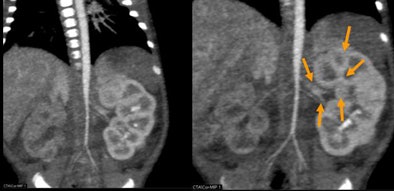

| Patient with stridor and giant cervical hemangioma was breathing continuously and not sedated during 320-detector-row CT, acquired in two rotations at 0.35 sec, 80 kV, 20 mA, and dose of 0.3 mSv. Below, additional rotation allows reconstruction of images at multiple time points, revealing air trapping that would have been missed at single-rotation scan. |